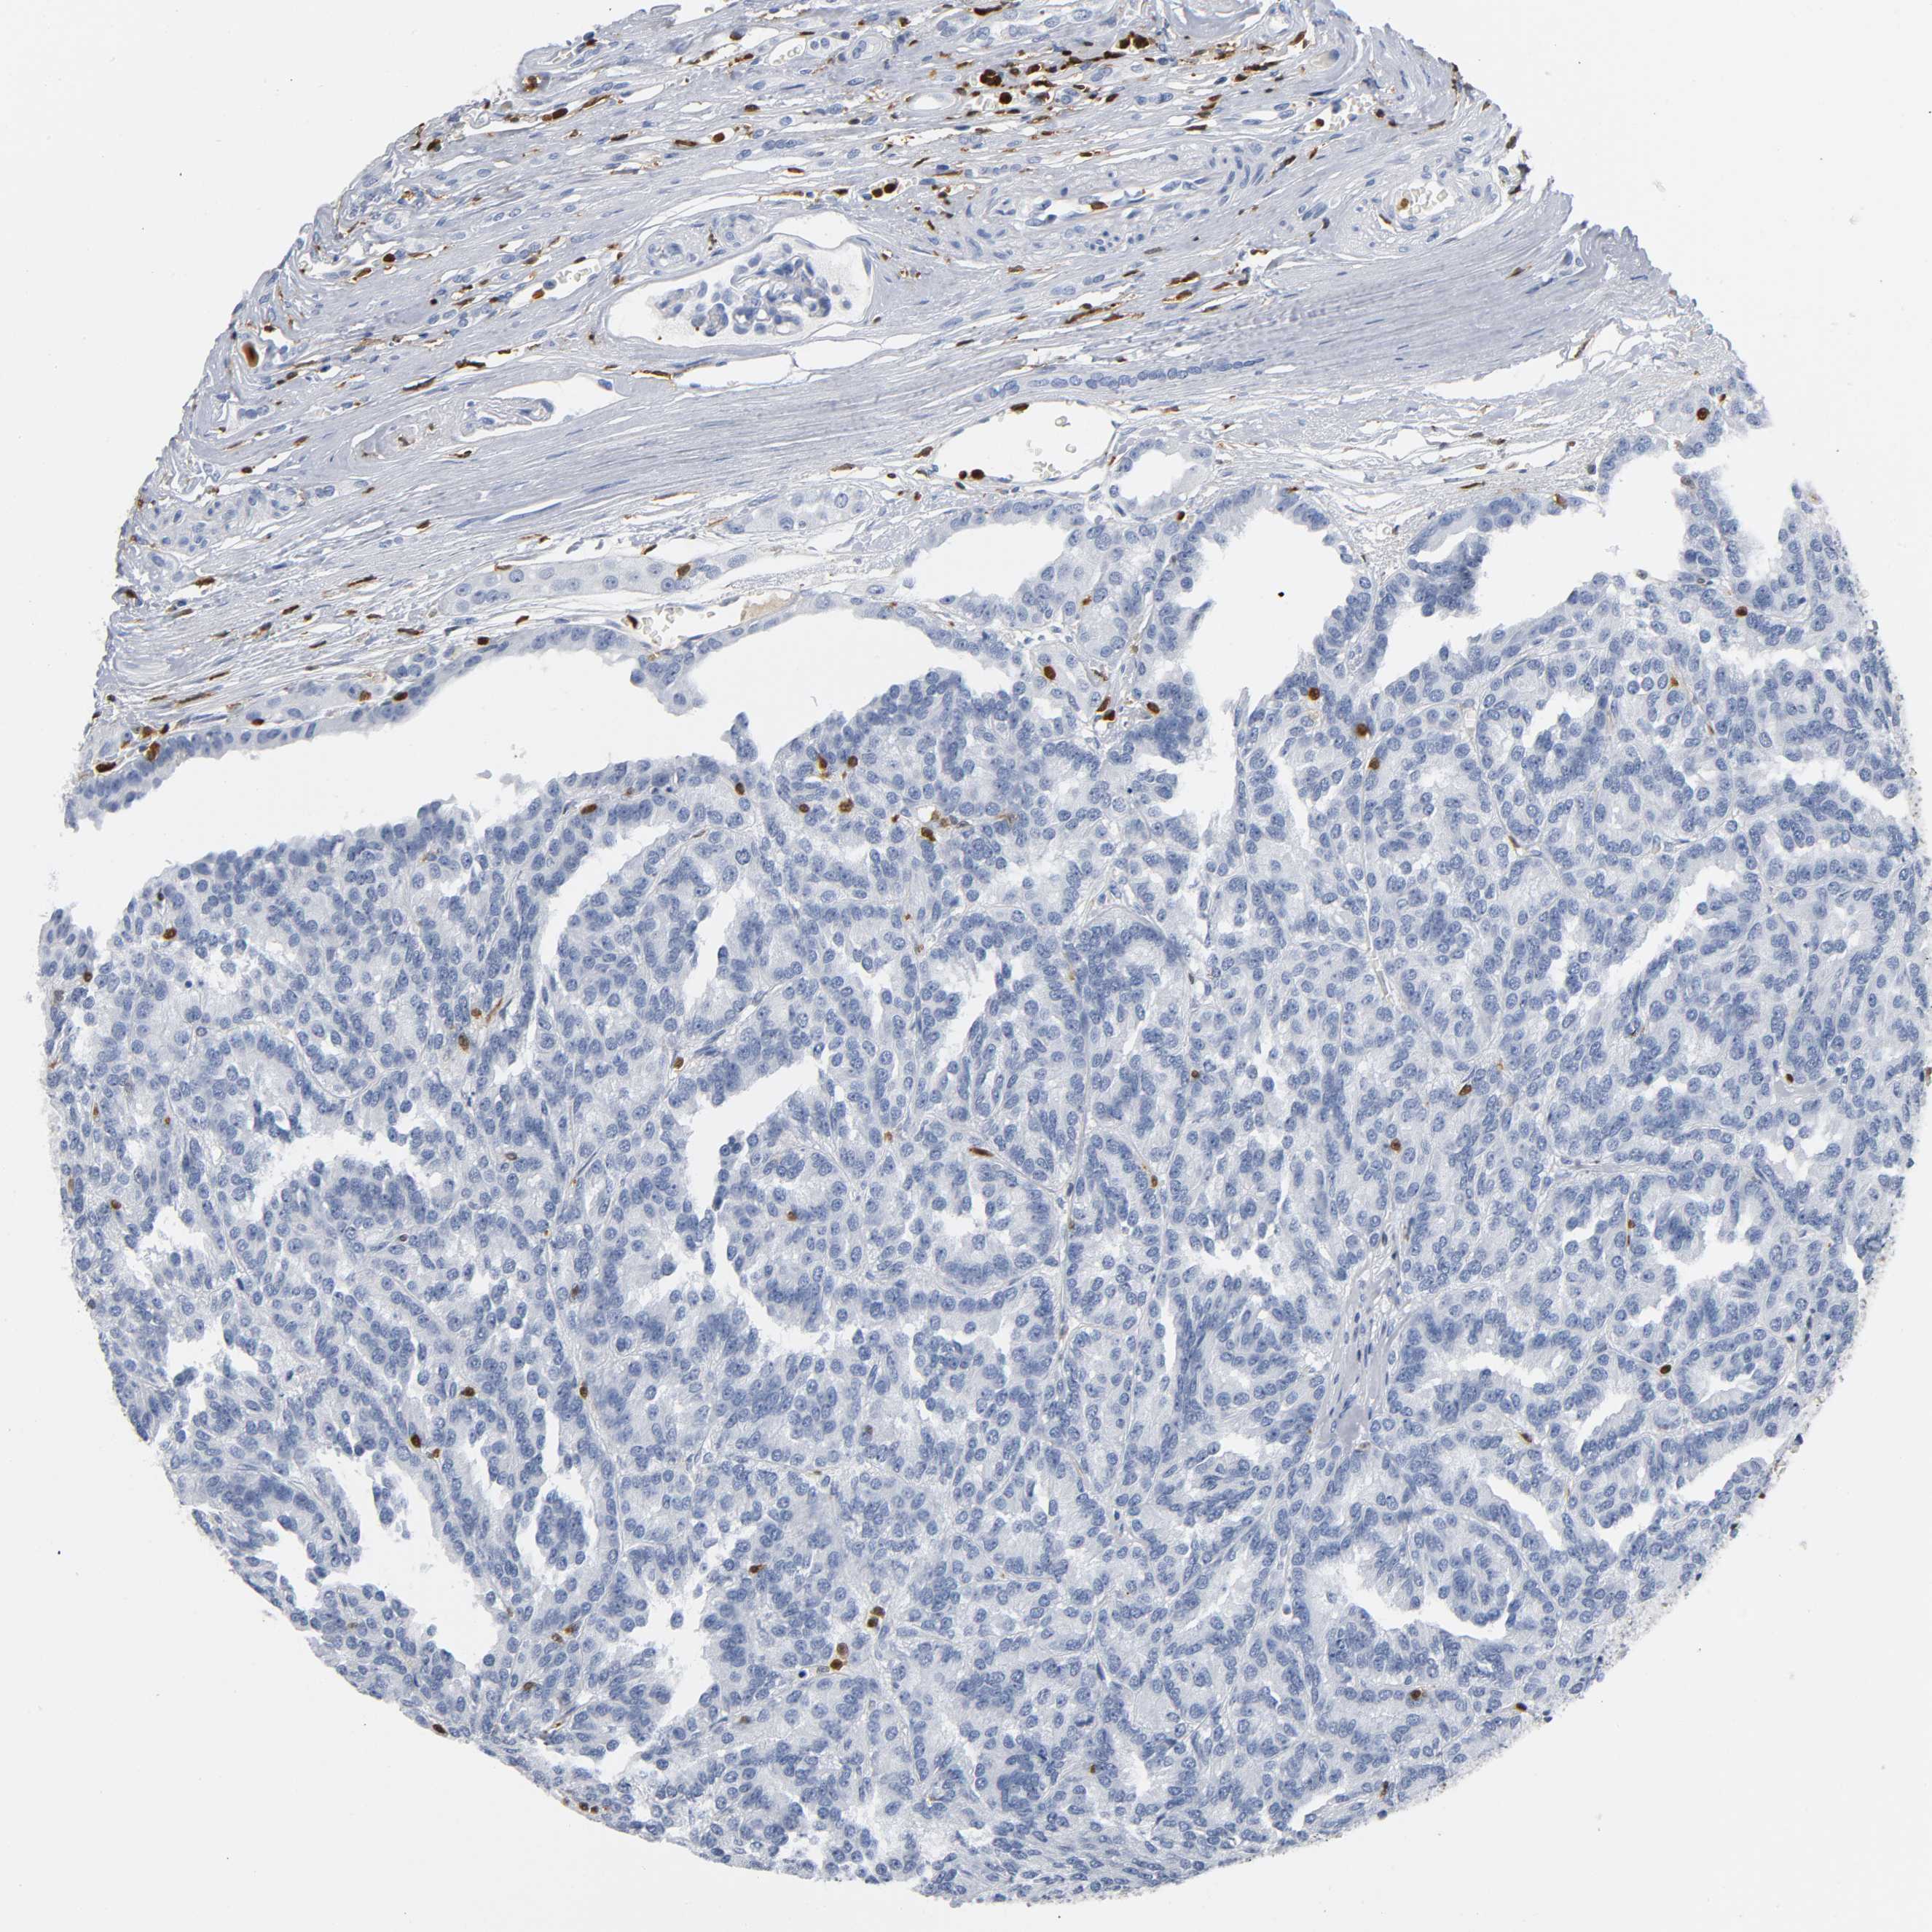

KIDNEY RENAL CLEAR CELL CARCINOMA (VALIDATION) - Interactive survival scatter ploti

The Survival Scatter plot shows the clinical status (i.e. dead or alive) for all individuals in the patient cohort, based on the same data that underlies the corresponding Kaplan-Meier plots. Patients that are alive at last time for follow-up are shown in blue and patients who have died during the study are shown in red.

The x-axis shows the expression levels (FPKM) of the investigated gene in the tumor tissue at the time of diagnosis. The y-axis shows the follow-up time after diagnosis (years). Both axes are complimented with kernel density curves demonstrating the data density over the axes. The top density plot shows the expression levels (FPKM) distribution among dead (red) and alive patients (blue). The right density plot shows the data density of the survived years of dead patients with high and low expression levels respectively, stratified using the cutoff indicated by the vertical dashed line through the Survival Scatter plot. This cutoff is automatically defined based on the FPKM cutoff that minimizes the p-score. The cutoff can be changed by dragging the vertical line or by entering a cutoff value in the square labeled "Current cut-off".

Under the Survival Scatter plot the p-score landscape (black curve; left axis) is shown together with dead median separation (red curve; right axis). Dead median separation is the difference in median mRNA expression between patients who have died with high and low expression, respectively. It is calculated as follows: median FPKM expression of dead patients with high expression - median FPKM expression of dead patients with low expression. This is intended to aid the user in visually exploring custom cutoffs and the associated p-scores and dead median separation.

Individual patient data is displayed and can be filtered by clicking on one or more of the category buttons on the top of the page. Categories describing expression level and patient information include: high, low, alive, dead, female, male and tumor stages. The scale of the x-axis can be toggled between linear and log-scale by clicking on the "x log" button. Mouse-over function shows TCGA ID, patient information and mRNA expression (FPKM) for each patient.

& Survival analysisi

Kaplan-Meier plots summarize results from analysis of correlation between mRNA expression level and patient survival. Patients were divided based on level of expression into one of the two groups "low" (under cut off) or "high" (over cut off). X-axis shows time for survival (years) and y-axis shows the probability of survival, where 1.0 corresponds to 100 percent.

DOK2 is not prognostic in Kidney Renal Clear Cell Carcinoma (validation)

Best expression cut offi

Based on the FPKM value of each gene, patients were classified into two groups and association between prognosis (survival) and gene expression (FPKM) was examined. The best expression cut-off refers the FPKM value that yields maximal difference with regard to survival between the two groups at the lowest log-rank P-value. Best expression cut-off was selected based on survival analysis .

When clicking on this number, the vertical dashed line indicating cut-off, the interactive survival plot, and the Kaplan-Meier curve will be adjusted to show results based on the best expression cut-off.

: 11.28

P scorei

Log-rank P value for Kaplan-Meier plot showing results from analysis of correlation between mRNA expression level and patient survival.

N/A

TCGA RNA samplesi

RNA-seq data is reported as average FPKM (number Fragments Per Kilobase of exon per Million reads), generated by the The Cancer Genome Atlas (TCGA) .

Normal distribution across the dataset is visualized with box plots, shown as median and 25th and 75th percentiles. Points are displayed as outliers if they are above or below 1.5 times the interquartile range. FPKM values of the individual samples are presented next to the box plot.

Average pTPM 11.3

Number of samples 100